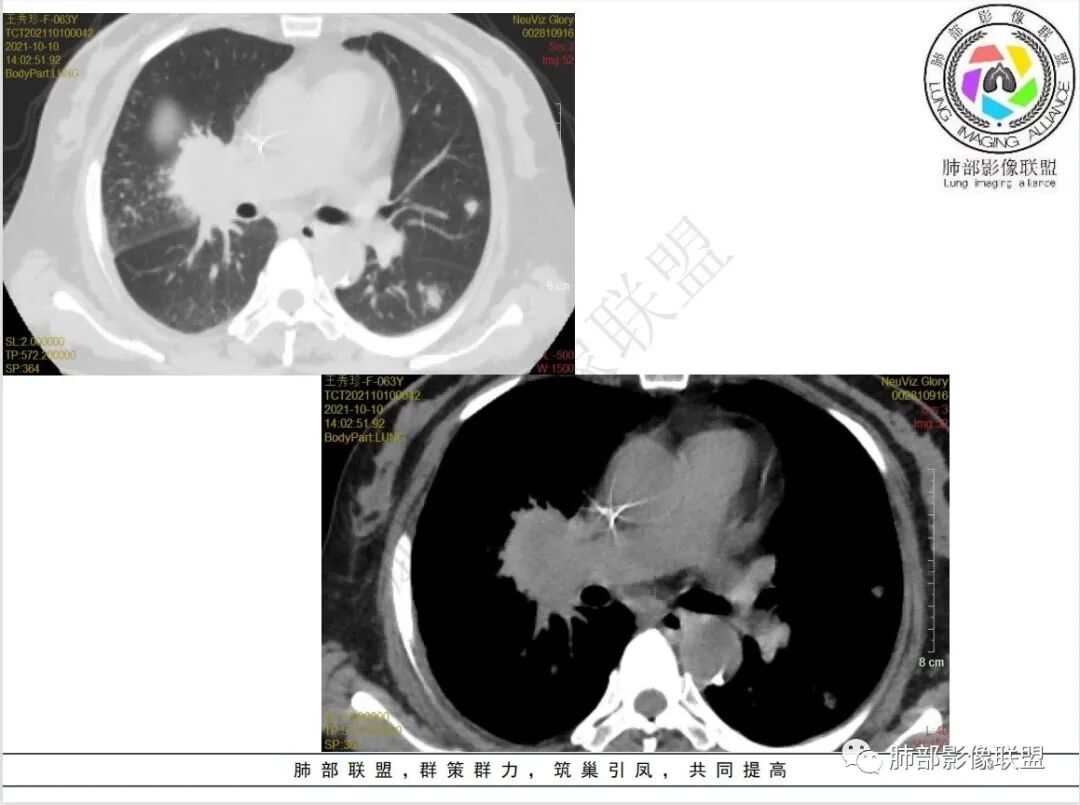

1.老年女性,既往白血病病史,并多次化疗,骨髓抑制明显。

2.此次急性起病,高热并咳嗽,偶有血性痰。

3.实验室培养出多种病原菌,并针对性覆盖多种抗感染药物,但肺部病灶却不断进展。

4.白血病化疗后,CT上出现多发结节,边缘可见晕征,病灶内可见多发坏死,右肺中叶肺动脉可见充盈缺损,右肺中叶可见融冰征,右肺中叶肺动脉侵犯栓塞伴右肺中叶肺梗死,可符合真菌感染。

6.肺曲霉病典型的CT表现是结节周围有磨玻璃样的晕征表现,或胸膜为宽基底的楔形实变。晕征表现为曲菌感染的肺结节伴梗死和凝固性坏死,周围有肺泡出血。最终可出现空泡征象,并可观察到中央坏死组织与周围肺实质分离形成空气新月征。

晕征已被认为是侵袭性曲菌病的早期征象之一。